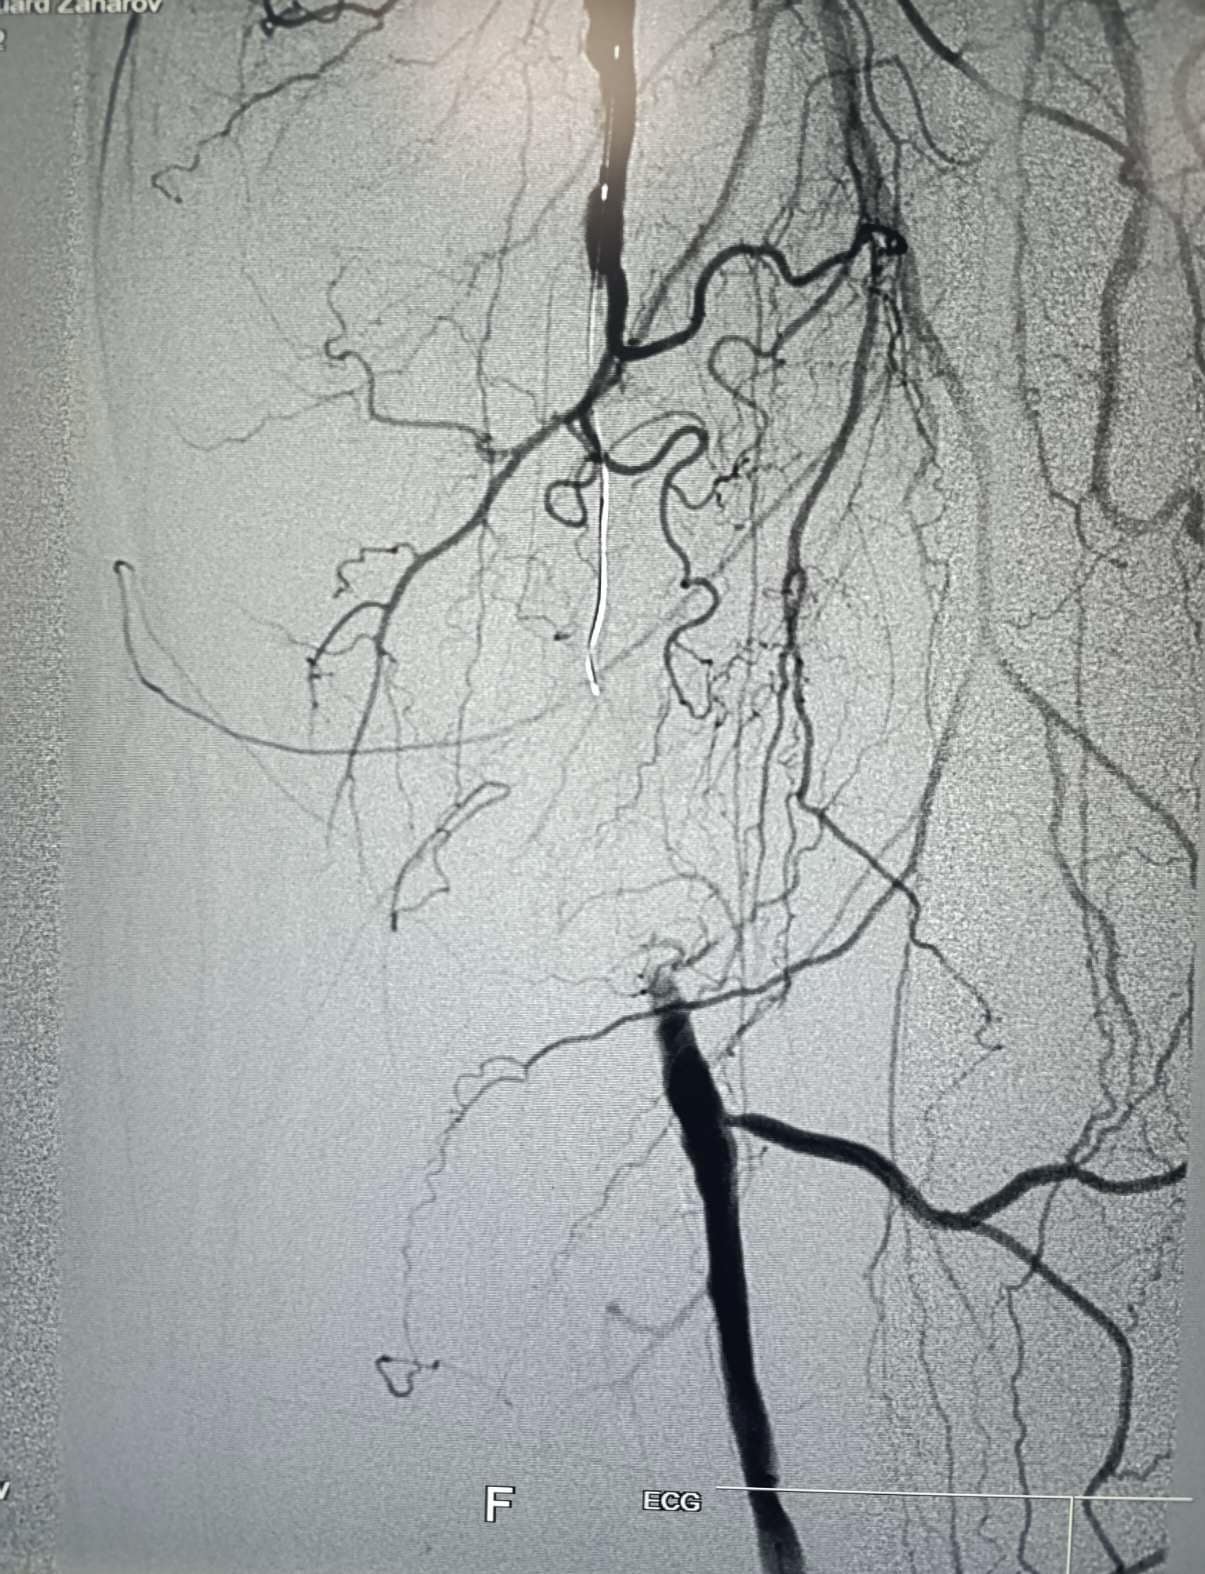

«Операция была проведена смешанной бригадой интервенционных врачей и сосудистых хирургов 69-летнему пациенту с диагнозом прогрессирующая артериальная ишемия левой ноги, вызванная хронической сегментарной окклюзией поверхностной бедренной артерии», — сообщает администрация медицинского учреждения.

Минимально инвазивная и современная методика включала механическое удаление атеросклеротической бляшки, блокирующей кровоток, с использованием специализированной системы для атерэктомии, фильтра для защиты от эмболии и баллонного катетера с лекарственным препаратом. Процедура проводилась без имплантации стента и разрезов, что позволило сохранить анатомическую целостность артерии и обеспечить возможность проведения последующих процедур реваскуляризации.